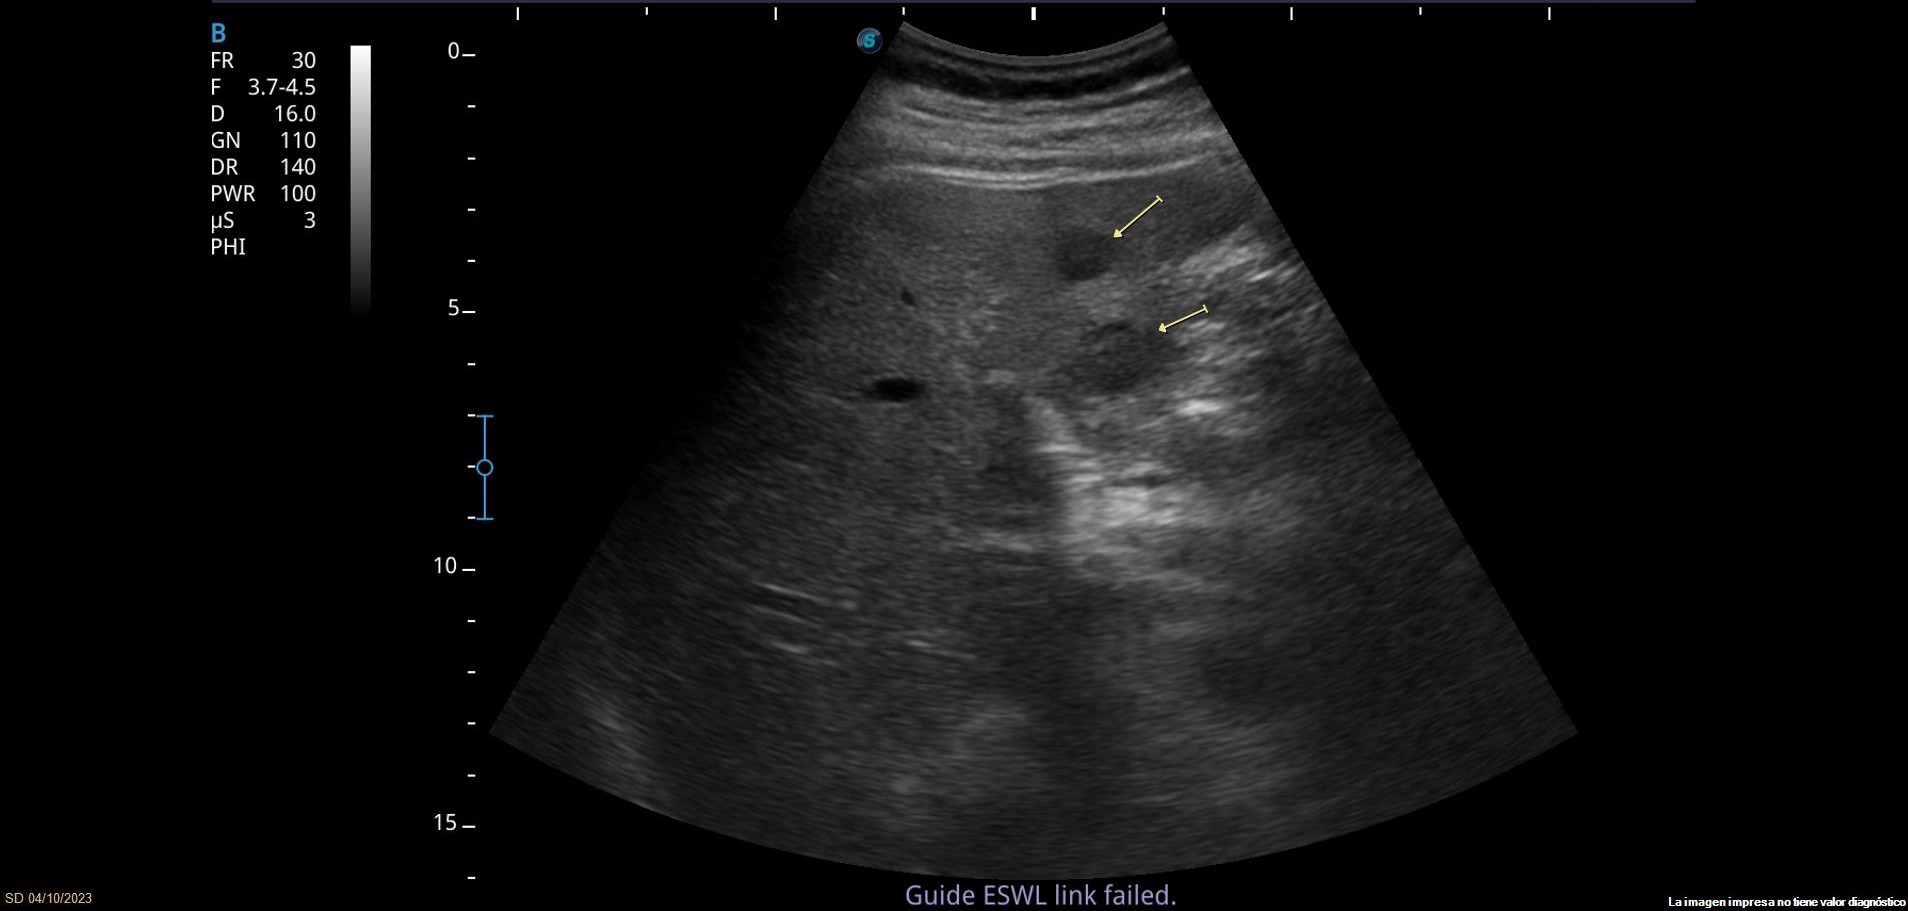

Se observan varias LOEs (lesiones ocupantes de espacio) hepáticas isoecoicas con parénquima hepático, la mayor de 3.5cm de diámetro, con leve vascularización. También se observa lesión hiperecoica con sombra posterior en parénquima hepático, sugerente de litiasis.